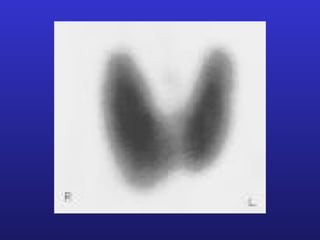

甲状腺形态

呈H形      左右两叶 + 峡部 + 锥状叶

( 70% )